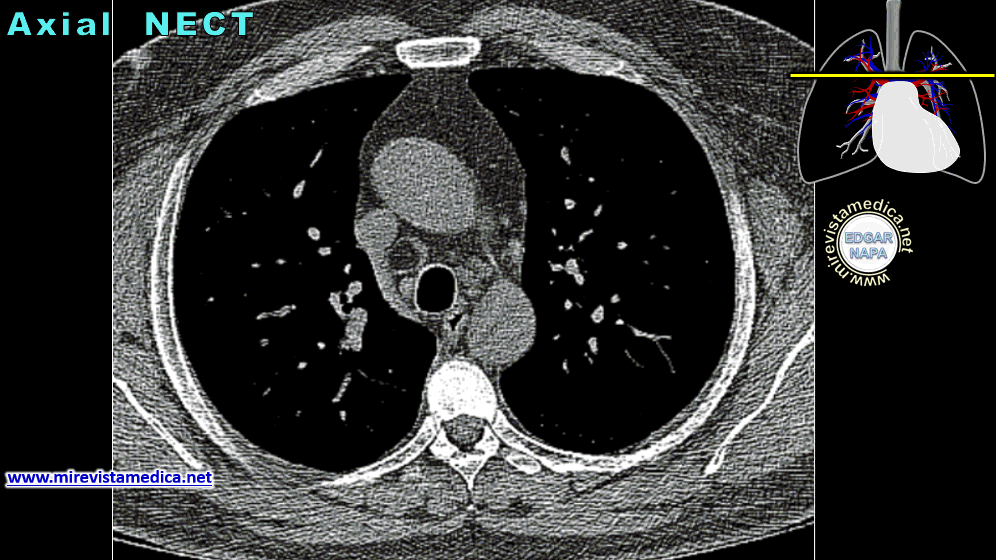

Esta rodeada por la serosa pericardio ; se ubica en el MEDIASTINO MEDIO entre los Pulmones y las coberturas pleurales.

Disposicion del corazon

Aurícula izquierda, es la cavidad más posterior del corazón, mientras que la punta del corazón (apex) es la parte mal caudal del ventrículo izquierdo se relaciona con el 5to espacio intercostal izquierdo.

Sus cavidades superiores (las aurículas) tienen orientación posterior y los ventrículos orientación anterior.